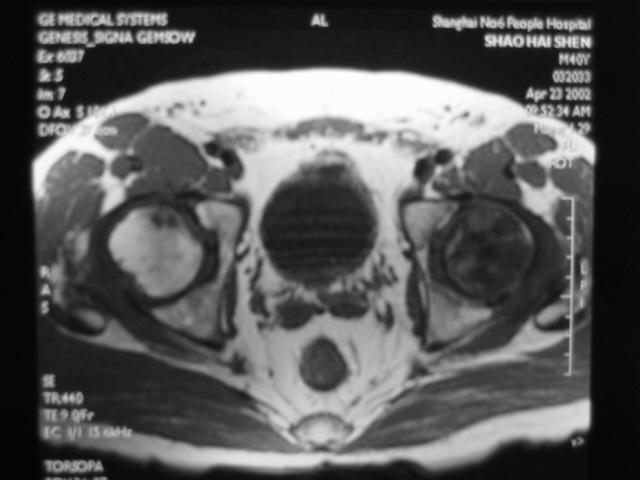

MRI诊断

Ⅳ期

关节软骨彻底破坏,髋关节间隙狭窄,合并关节退行性改变。

髋臼面软骨下骨质可出现囊性变,髋臼缘骨赘增生。

股骨头因骨坏死、囊变、骨折而显著塌陷、变形,受累范围可局限于股骨头上部或累及整个股骨头。

股骨头出现分节碎裂、骨折移位。